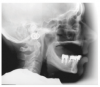

Class III relationship with a resorbed ridge and locators in the lower ridge.

Figure 13

Figure 13 shows a situation with a Class III ridge relationship, extensive bone loss in the upper arch opposing a locator-retained lower removable prosthesis. Figure 14 shows that the occlusal contact between the prosthetics is limited to the posterior teeth.